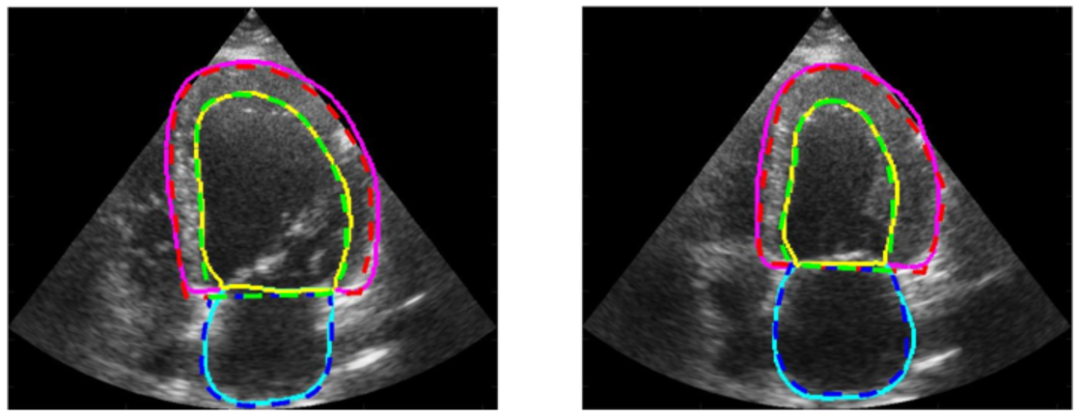

2. CAMUS 心脏超声图像数据集

该数据集包含从 500 名患者获取的二维心尖四腔和两腔视图序列,这些数据在法国圣艾蒂安大学医院采集,并经过完全匿名化处理,以确保患者的隐私和数据的合规性。每张图像都经过专业医学人员的精确标注,涵盖了左心室心内膜、左心室心外膜以及左心房的轮廓信息,这些详细的标注为研究人员提供了丰富的训练和验证资源。

直接使用:https://go.hyper.ai/iYtn2

数据集示例